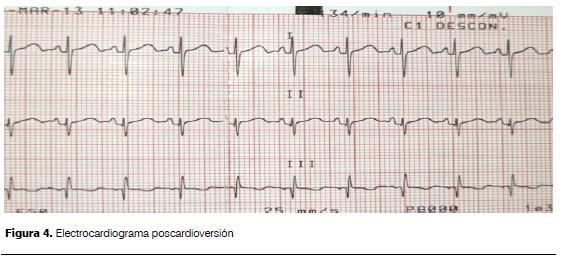

Se realizó adenosina no retomando ritmo sinusal, objetivando como se ve en la figura 3 espaciamiento de los complejos QRS y la presencia de ondas en dientes de sierra características del flutter auricular, se realizó entonces cardioversión eléctrica sincronizada con 5 J, efectiva, revirtiendo a ritmo sinusal (figura 4).

La administración de adenosina produce bloqueo del nodo aurículo-ventricular no permanente permitiendo identificar pacientes con arritmias en los que la onda P está enmascarada por el QRS o la onda T(13); la no respuesta a la dosis inicial y la evidencia de ondas en dientes de sierra inmediato y fugaz a su administración permitió confirmar el diagnóstico de flutter auricular, procediendo entonces a realizar la cardioversión eléctrica sincronizada, tratamiento óptimo en el período posnatal(13,14).

El correcto control del embarazo permite diagnosticar en forma temprana las arritmias cardíacas, permiten a su vez el tratamiento fetal y evitar las complicaciones graves como el hidrops. El tratamiento intrauterino y la interrupción del embarazo están claramente vinculadas a la edad gestacional. La cardioversión eléctrica es el tratamiento de elección del flutter neonatal presentando un buen pronóstico en ausencia de cardiopatía estructural.